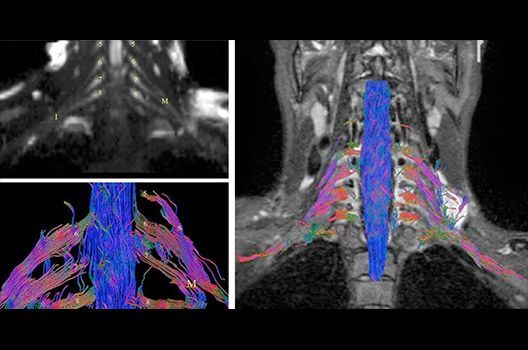

Die Magnetresonanztomographie (MRT) ist ein Verfahren, bei dem durch magnetische Kräfte Bilder des Körperinneren angefertigt werden. In der Neuroradiologie können manchmal kleinste Veränderungen schwere Folgen haben; daher forschen wir an der Entwicklung hochauflösender MRT-Sequenzen, mit denen diese Prozesse und auch einzelne Nervenfaserbahnen sichtbar gemacht werden können. Darüber hinaus sind bei vielen Erkrankungen des Gehirns die Blutgefäße betroffen. Daher arbeiten wir an der Neu- und Weiterentwicklung von MRT-Sequenzen zur Darstellung der Blutgefäße und zur Blutflussanalyse (sog. „Angio-MRT“). Einen besonderen Forschungsschwerpunkt unserer Klinik stellen die MR-Protonenspektroskopie und die funktionelle MRT dar, mit denen die Analyse einzelner chemischer Substanzen im Hirngewebe oder die Darstellung ausgewählter Hirnfunktionen möglich ist.